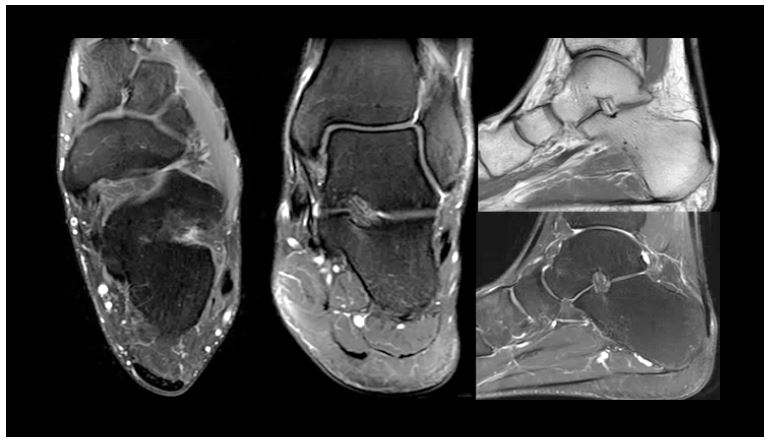

Клінічні зображення МСК з використанням 16-канальної гнучкої котушки

Рис. 13. Зображення передньої частини стопи

Рис. 12. Зображення щиколотки